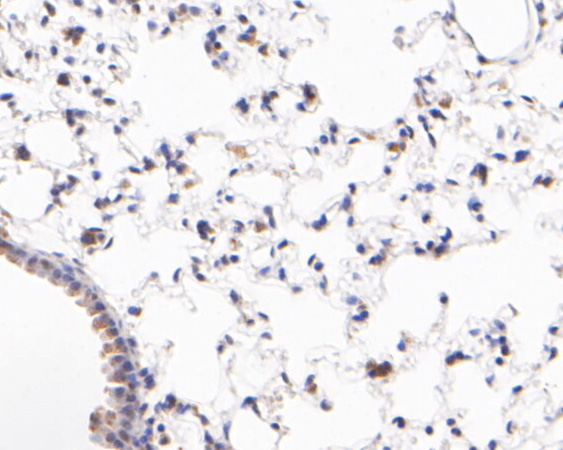

|   | Fig5: Immunohistochemical analysis of paraffin-embedded mouse lung tissue using anti-ID2 antibody. The section was pre-treated using heat mediated antigen retrieval with sodium citrate buffer (pH 6.0) for 20 minutes. The tissues were blocked in 5% BSA for 30 minutes at room temperature, washed with ddH2O and PBS, and then probed with the primary antibody (R1510-6, 1/400) for 30 minutes at room temperature. The detection was performed using an HRP conjugated compact polymer system. DAB was used as the chromogen. Tissues were counterstained with hematoxylin and mounted with DPX. |